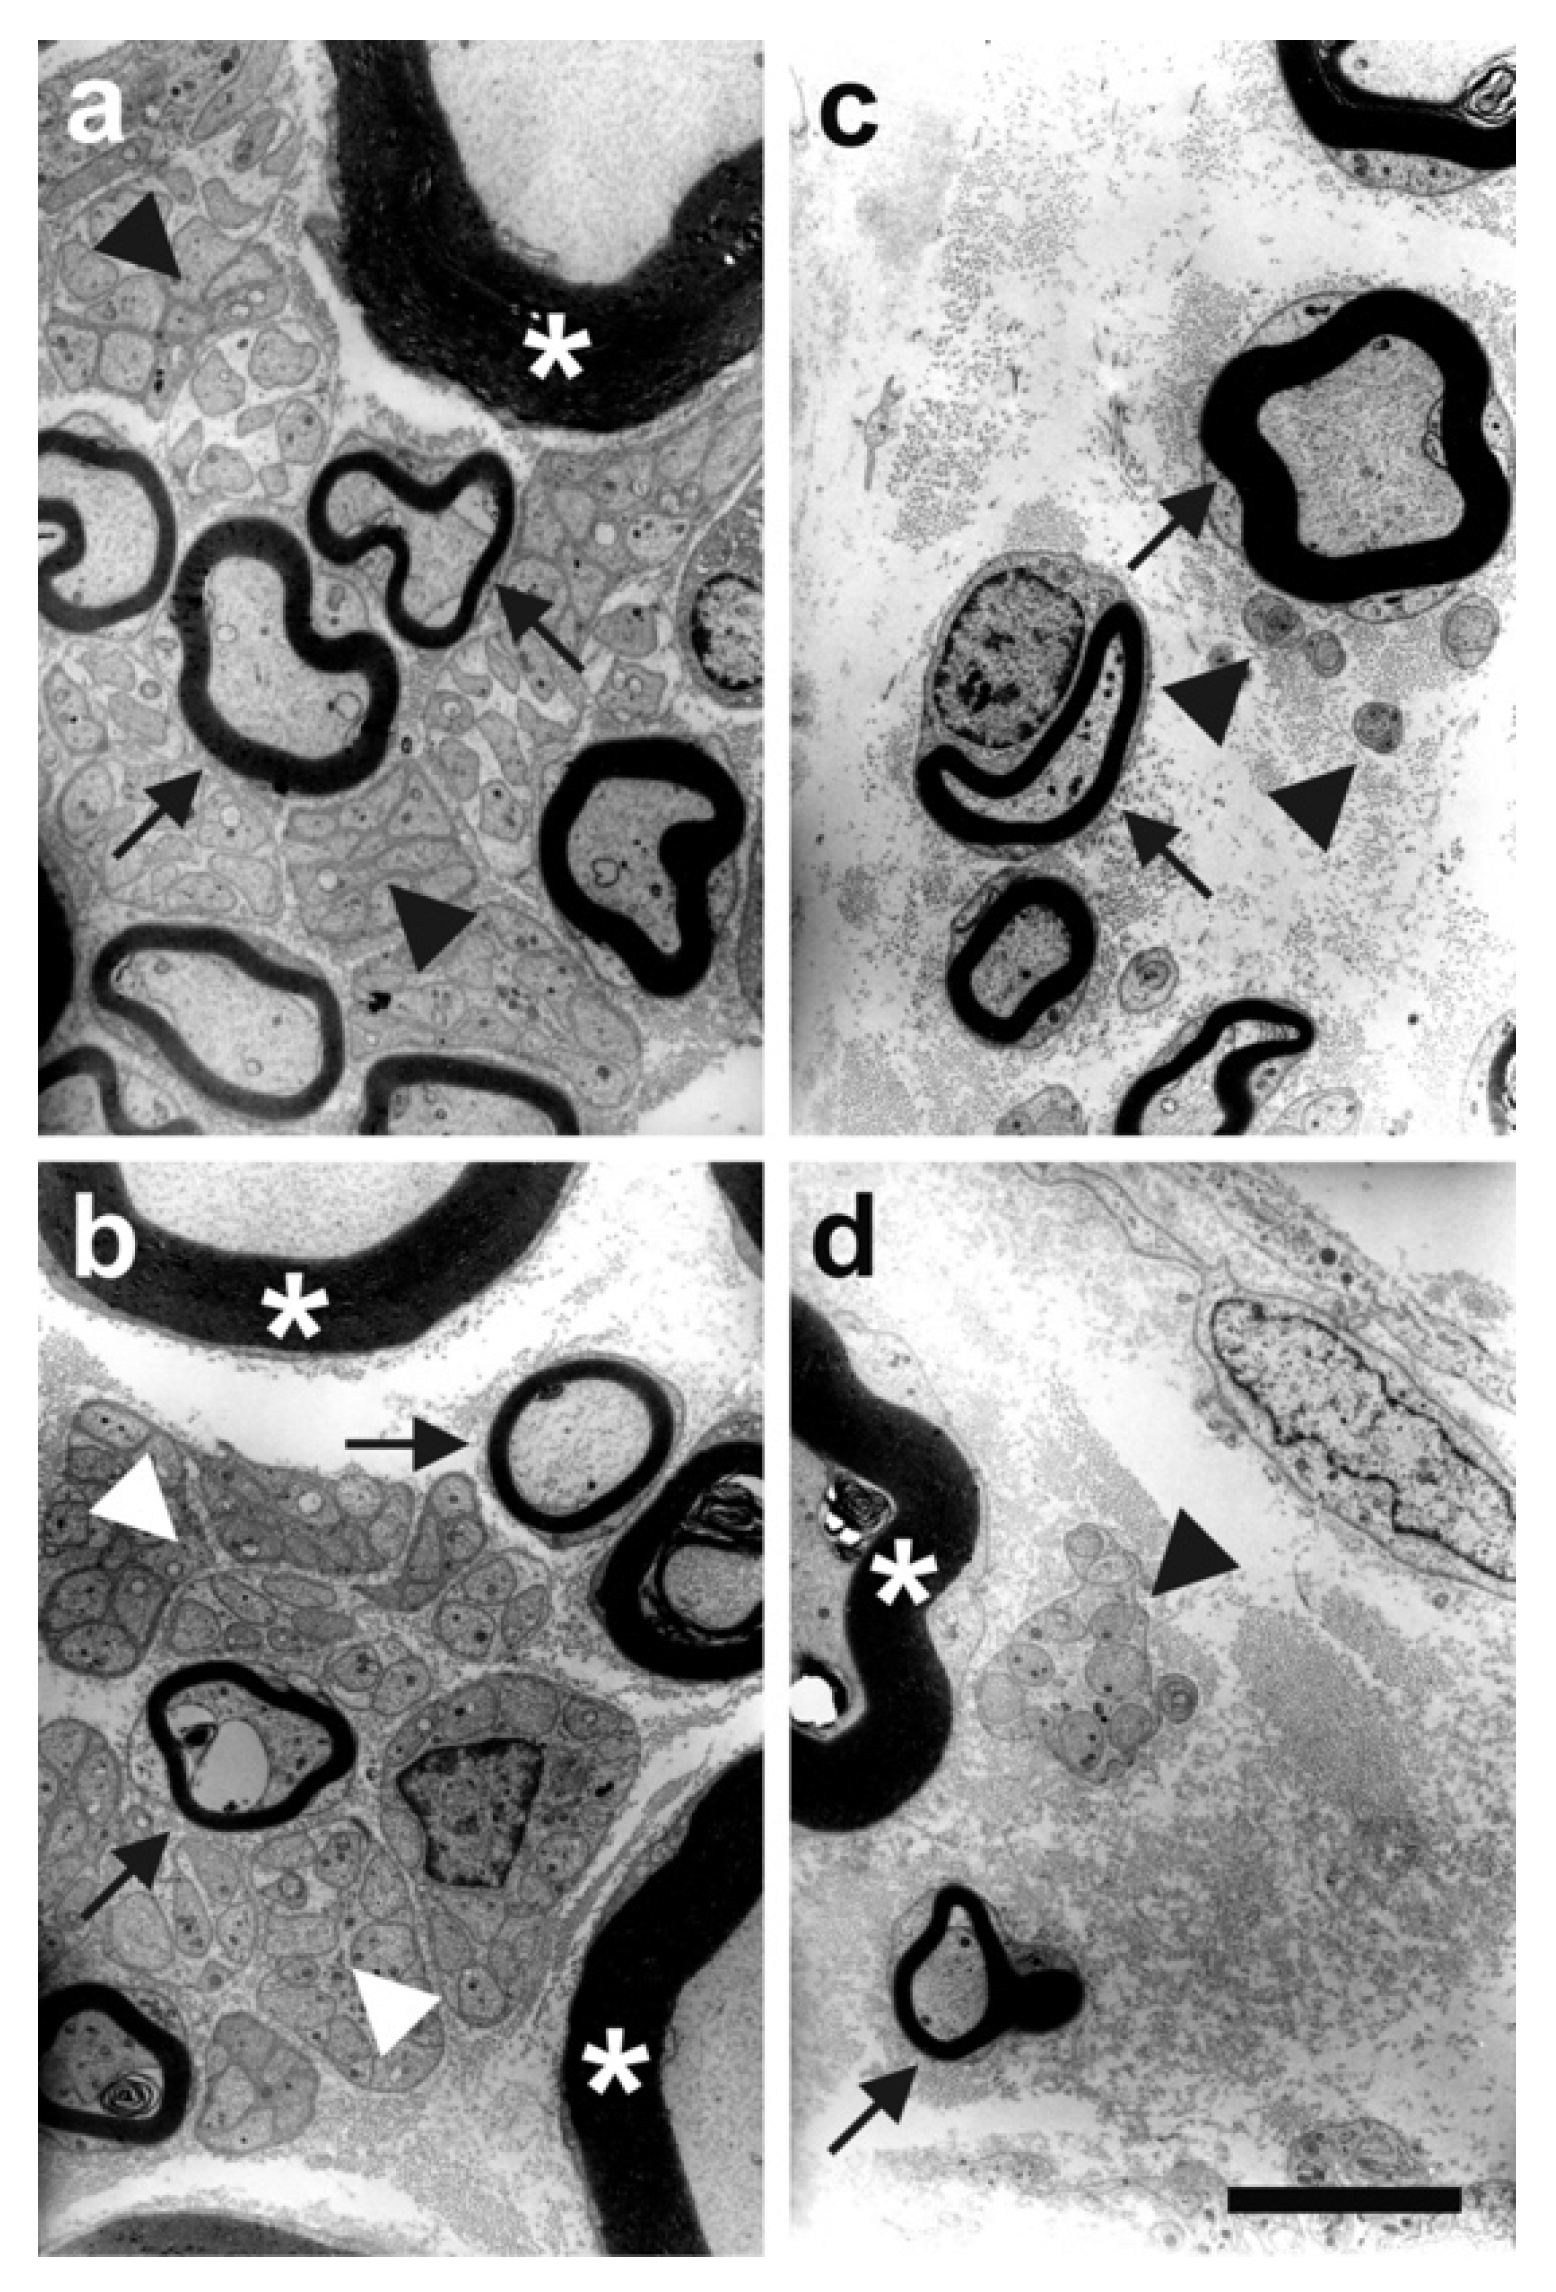

| Rat | Plantar skin of hind paw | Nearly complete degeneration of epidermal nerve fibers, as indicated by the significant loss of PGP9.5 and CGRP immunoreactivity | [51] |

| Rabbit | Ventral side of the right distal femur | Selective and substantial loss of unmyelinated nerve fibers within the femoral nerve of treated hind limb | [56] |

| Horse | Left forelimb | Significant lower SNCV ‡ in treated medial and lateral palmar digital nerves along with a severe disruption of myelin sheath | [130] |